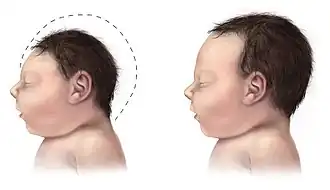

Baby met microcefalie (l) vergeleken met een normaal hoofd

Microcefalie is een afwijking van het centrale zenuwstelsel waarbij de schedelomvang te klein is. Het is meestal een aangeboren aandoening. De hersenen ontwikkelen zich niet goed waardoor de schedel ook kleiner blijft. Vaak is er sprake van een verstandelijke beperking.